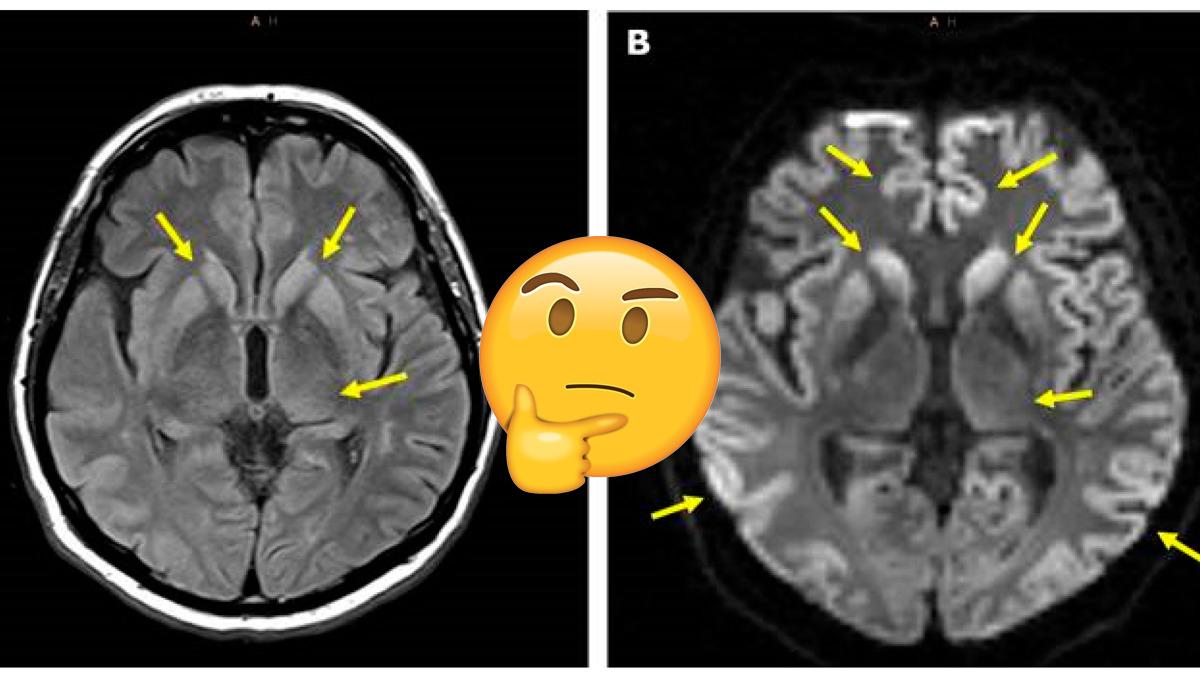

Evet evet yanlış duymadınız. Creutzfeldt-Jakob hastalığı, insan beyninde delikler yaratıyor. Elbette rahatsızlık kadar insan vücuduna olan etkileri de bir o kadar garip.

Beyinde delikler ortaya çıkmasına sebep olan bu rahatsızlık, aslında çok nadir görülüyor. Dünya çapında yaklaşık 1 milyon kişiden sadece 1 kişiyi etkiliyor. Erkekler ve kadınların bu hastalığa yakalanma ihtimali ise tamamen eşit.

Öte yandan bu rahatsızlığa, beyindeki prionlar yani anormal proteinler sebep oluyor. Bu proteinler de dokularda ne yazık ki geri döndürülmesi imkânsız hasarları beraberinde getiriyor.

Aynı zamanda beynindeki çoğu nöronun düzgün çalışmamasına ve ölmesine sebep olan sünger benzeri delikleri yaratıyor.

Beyinde delikler oluşmasına neden olan bu rahatsızlığın maalesef bir tedavisi yok.